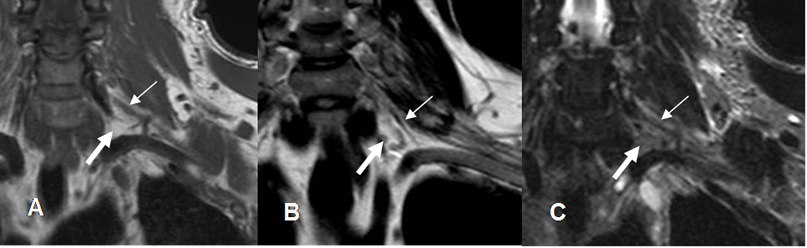

Fig 2. Cojinete graso.

A: RM coronal en T1, B: RM coronal en T2 y C: RM coronal en STIR. Cojinete graso normal hiperintenso en T1 y T2 y que suprime en STIR (Flechas gruesas), que contiene las raíces nerviosas. (Flechas delgadas).